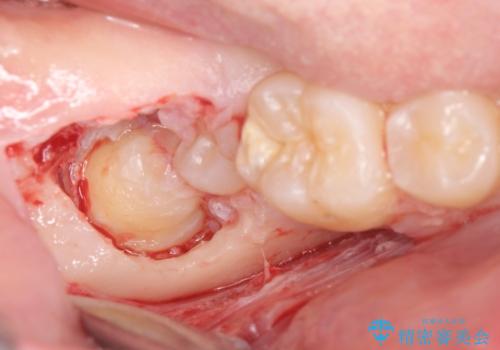

- 右上下親知らずを抜きたいとの事で来院。

レントゲンを確認したとこと完全埋伏歯でした。

CTで神経の位置などを確認し、抜歯術を行いました。

無事抜歯を行うことができました。